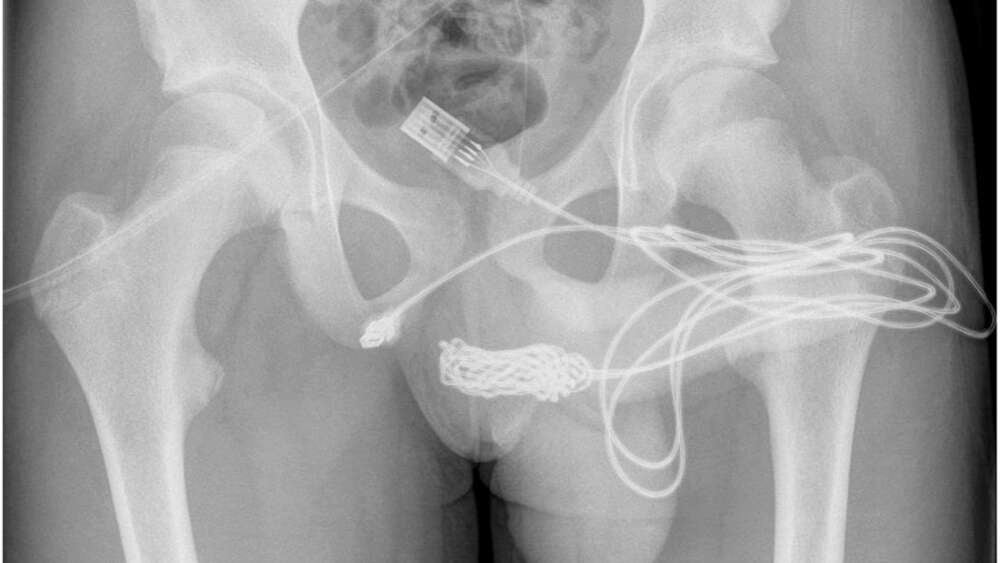

Se encontró que los dos puertos distales del cable USB sobresalían del meato uretral externo, mientras que la parte media del cable anudado permanecía dentro de la uretra. El paciente era un adolescente sano y por lo demás en forma, sin antecedentes de trastornos de salud mental.

En ambos intentos fallaron debido al nudo, el mismo que se ve en la radiografía. Las imágenes de la situación del cable mostraron que la cirugía era necesaria. Según los autores:

Se hizo una incisión longitudinal penoescrotal sobre el cuerpo extraño palpable y se llevó a cabo una disección cuidadosa a través de los tejidos más profundos, dividiendo el músculo bulboesponjoso. Ambos extremos del alambre se sacaron con éxito a través del meato uretral externo.